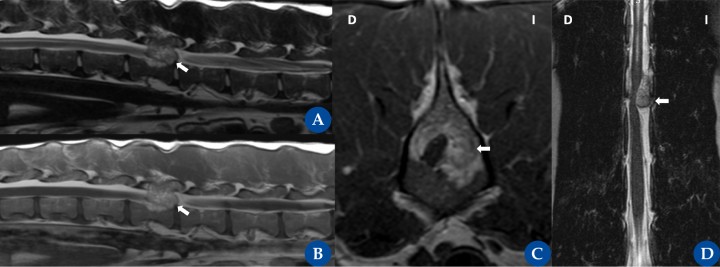

Tumor espinal extradural (osteosarcoma). Resonancia magnética: plano sagital ponderado en T2 (A), ponderado en T1 post contraste (B), transversal ponderado en T1 post contraste (C) y dorsal ponderado en T2 (D) en un galgo, hembra castrada de 6 años, con una historia crónica progresiva, de 3 meses de evolución, desde la cirugía de castración, de ataxia propioceptiva de las extremidades pélvicas y paraparesia ambulatoria marcada. Se observa una masa de gran tamaño, extradural, que ocupa espacio dentro de la cara izquierda del canal vertebral al nivel de L2, y que se extiende desde el aspecto medial de L2 hasta el nivel del espacio del disco intervertebral. La lesión ocupante de espacio está bien definida y tiene forma ovoide. La médula espinal está marcadamente desplazada hacia el lado contralateral y marcadamente comprimida con una forma irregular. El hueso circundante del cuerpo vertebral, los pedículos vertebrales y la lámina vertebral tienen alteración de la señal en T2 y T1. La superficie cortical está principalmente lítica y destruida. La intensidad de la señal en T2 y T1 se extiende a lo largo del proceso espinal elevando la musculatura epaxial. No se aprecia un realce de contraste. El canal central de la médula espinal está moderadamente dilatado cranealmente (D) a la lesión que ocupa el espacio. La citología con aguja fina (ecoguiada) fue compatible con un osteosarcoma.